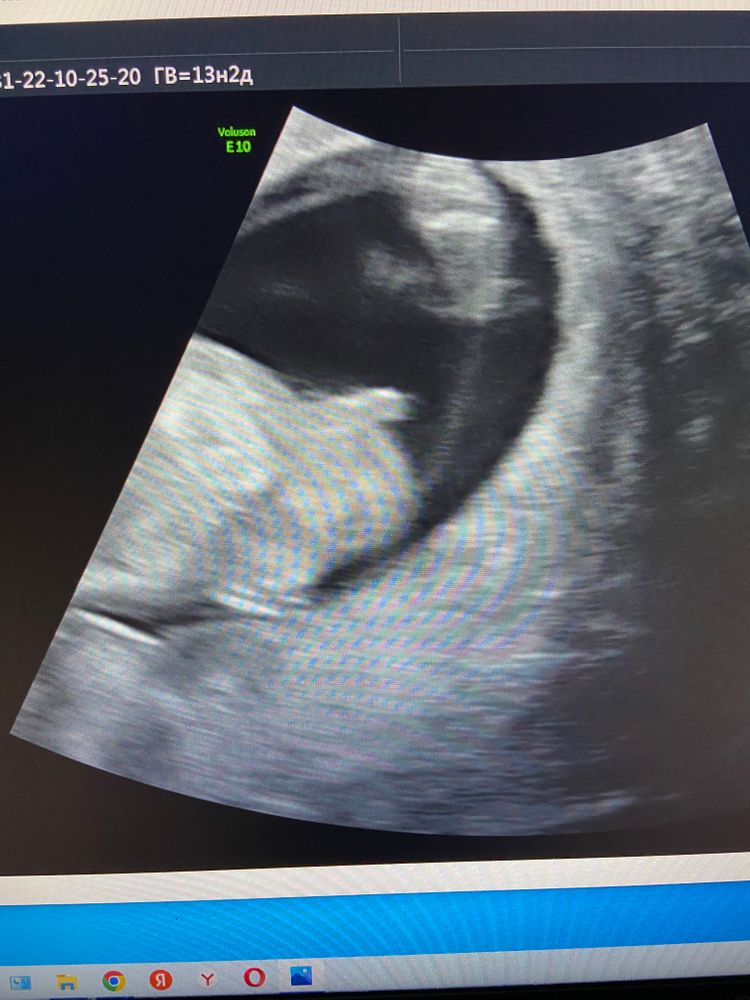

Так это ещё половой бугорок. Мне кажется у вас девочка.

Olga dey, так оно и есть. Был виден половой бугорок, на сроке 13 недель одинаковый и у мальчиков и у девочек

Одной мне кажется что мальчик?

Ирина Матвеева скоро стану мамой , нет, не одной, врачу-узи тоже